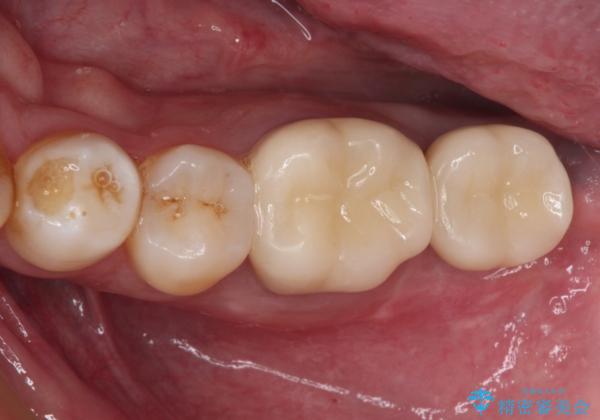

- 近医にて奥歯の抜歯が必要と言われたとのことで来院された患者様です。

診査の結果、歯が破折しており、抜歯が必要な状態でした。

最後方歯であるため、入れ歯かインプラントかどちらかの補綴治療を行うこととなりますが、ご希望によりインプラント補綴治療を行うこととしました。

インプラントにはストローマン社のSLActiveを使用し、埋入から補綴までおよそ3か月と、短期間で治療を進めることができました。